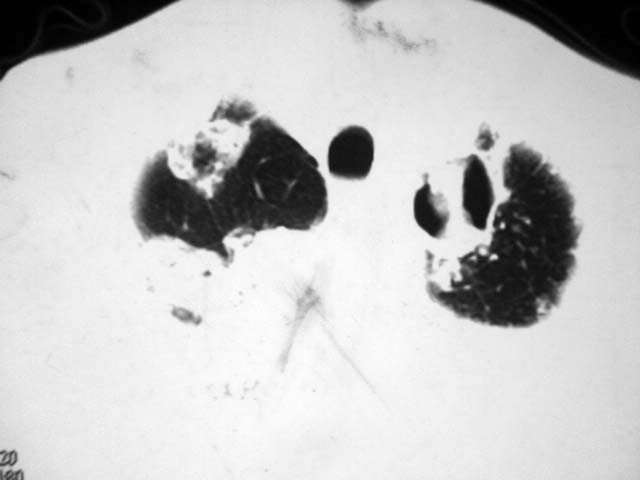

2、双肺见多发片状及结节状高密度影,大多数病灶中心均见“空泡征”。

3、纵隔内淋巴结肿大。

以上三点符合肺泡细胞癌的影像表现。

结果:两肺继发性肺结核并曲霉菌感染。